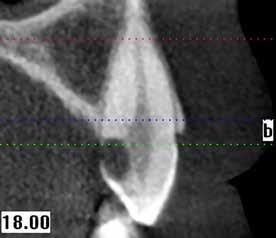

A maradó fogak gyökérreszorpciója patológiás folyamat. Az elváltozások elhelyezkedése alapján csoportosíthatjuk őket külső és belső reszorpciós folyamatokra. A külső gyökérreszorpciók egyre gyakrabban diagnosztizált formája a külső nyaki reszorpció (angolul External Cervical Resorption, ECR) [1. és 2. kép]. Az ECR egy komplex elváltozás, amely egyszerre érintheti a fog keményszöveti állományát, a parodontális szöveteket és előrehaladott esetben a pulpaszövetet is. A modern diagnosztikai eszközöknek köszönhetően egyre gyakrabban és egyre korábban kerül diagnosztizálásra ez a típusú lézió, így a kezelése is egyre inkább a mindennapi klinikum részévé válik az endodonciával foglalkozó kollégák számára. A 3 dimenziós diagnosztikai eszközök terjedésével felmerült az igény egy 3 dimenziós klasszifikációra. Patel és munkatársai 2018-ban kidolgoztak egy új klasszifikációt, amely segít az elváltozások kategorizálásában és a kezelések tervezésében [1]. A téma aktualitását jól mutatja, hogy ezzel egy időben az ESE (European Society of Endodontology) is kidolgozott egy állásfoglalást a külső nyaki reszorpciók diagnosztikájával és terápiás lehetőségeivel kapcsolatban [2].

Ötvenes éveiben járó páciensünk rutinellenőrzésre érkezett rendelőnkbe. A vizsgálat során felfigyeltünk a jobb felső metszőfogán kialakult, íny alatti elváltozásra. A röntgenfelvételen jól látható a kis méretű (Patel 1Ad) reszorpciós elváltozás [3. kép]

Ötvenes éveiben járó hölgyet fogorvosa irányította hozzánk a bal alsó 4-es fogának nagy méretű reszorpciójával [9. kép]. A hölgy ragaszkodott foga megmentéséhez, így a kezelés megtervezéséhez CBCT felvételt készítettünk a fogról [10. kép]. A felvételen a Patel-féle klasszifikáció szerinti Patel 3Ap reszorpciós elváltozás látható. A szájüregi vizsgálat során a fog bukkális felszínén gyulladt ínyt, mély parodontális tasakot és a fog nyaki részén, a foganyagon átsejlő reszorpciós lacunát találtunk [11. kép]. A fog szenzibilitás vizsgálat során nem reagált hideg ingerlésre. A pulpális érintettség miatt elvégeztük a fog trepanálását, majd lebenyt alakítottunk a kavitás láthatóvá tételéhez [12. kép]

1. és 2. kép: Külső nyaki reszorpciós elváltozások CBCT képen.Kónuszos felépítmény kapcsolat